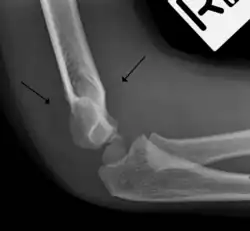

Fat pad sign

The fat pad sign, also known as the sail sign, is a potential finding on elbow radiography which suggests a fracture of one or more bones at the elbow. It may indicate an occult fracture that is not directly visible. Its name derives from the fact that it has the shape of a spinnaker (sail).[1] It is caused by displacement of the fat pad around the elbow joint. Both anterior and posterior fat pad signs exist, and both can be found on the same X-ray.

In children, a posterior fat pad sign suggests a condylar fracture of the humerus. In adults it suggests a radial head fracture.

The fat pad sign is invaluable in assessing for the presence of an intra-articular fracture of the elbow. An anterior fat pad is often normal. However a posterior fat pad seen on a lateral x-ray of the elbow is always abnormal. The patient will be unable to flex their elbow and requires orthopaedic input.[2]